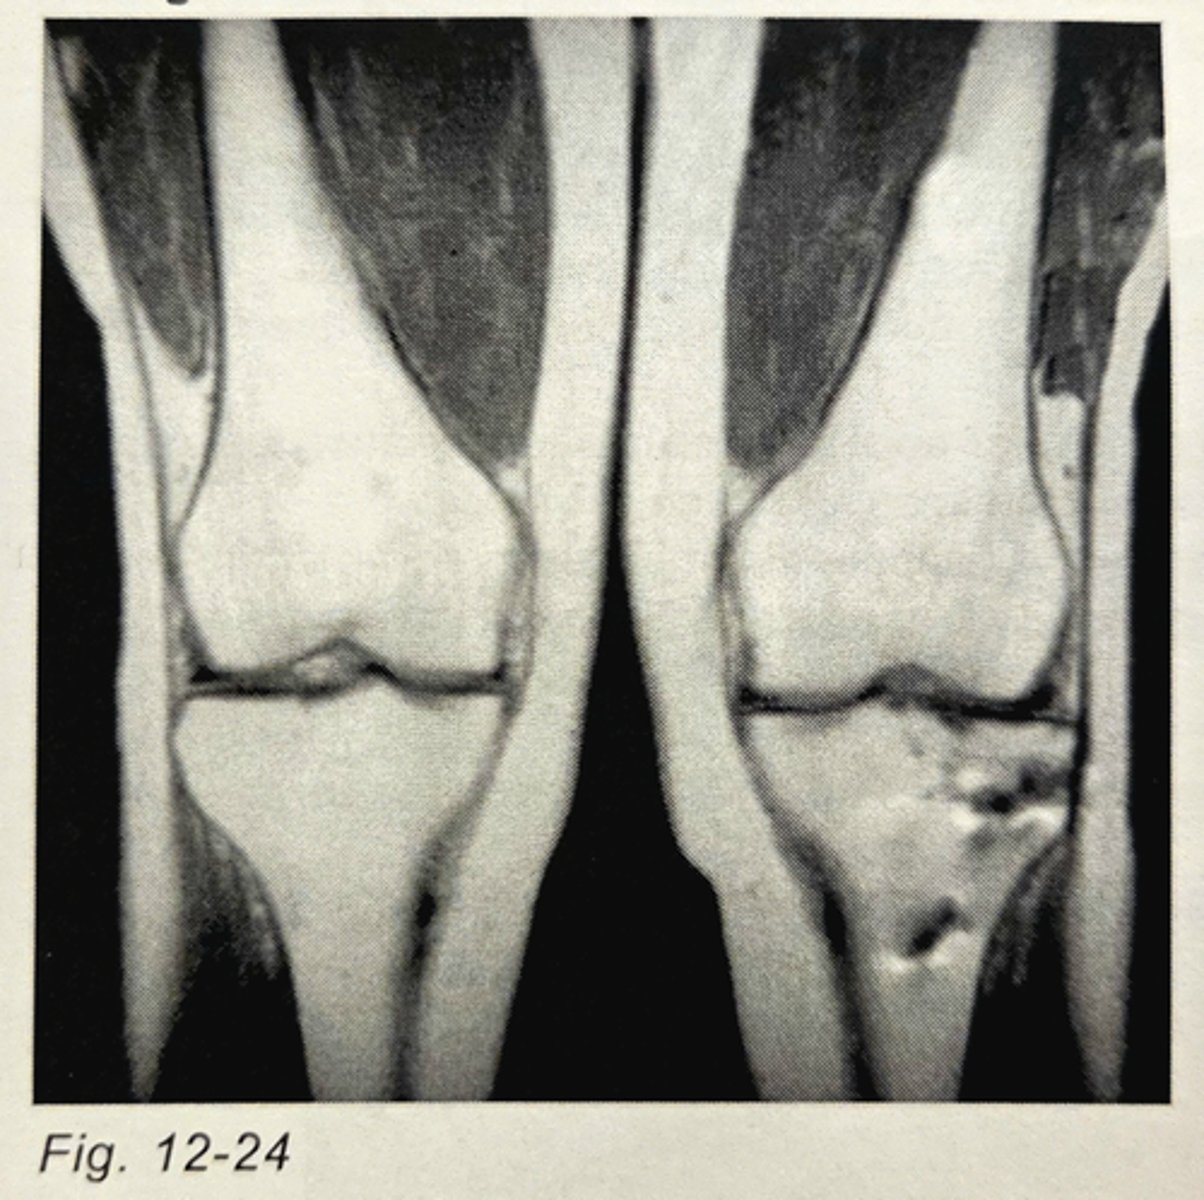

_______________ artifact is evident in the patient's left knee in Fig. 12-24.

Metal

The artifact in the conventional spin echo image in Fig. 12-24 can:

not be eliminated, since it is caused by metal bone pins